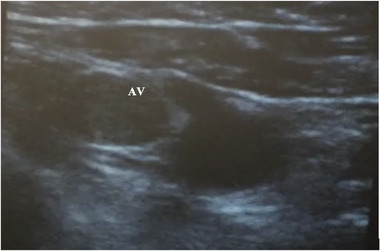

Background: There is limited real-world experience of the learning curve for ultrasound (US) guided axillary venous access for cardiac device implantation, and it is usually performed before cutaneous incision. We investigated the learning curve, radiation exposure, safety, and efficacy of US-guided venous access in standard workflow.

Methods: US-guided access was performed by an experienced electrophysiologist with no prior application of the technique by using a standard vascular US probe and minimal modification to workflow. The learning curve was evaluated using access time (needle-to-wire time). Complications were recorded until hospital discharge, and efficacy was defined by procedural success. Radiation dose savings were estimated based on fluoroscopy time for access, and a control group underwent conventional fluoroscopy landmark-guided access (n = 44 punctures).